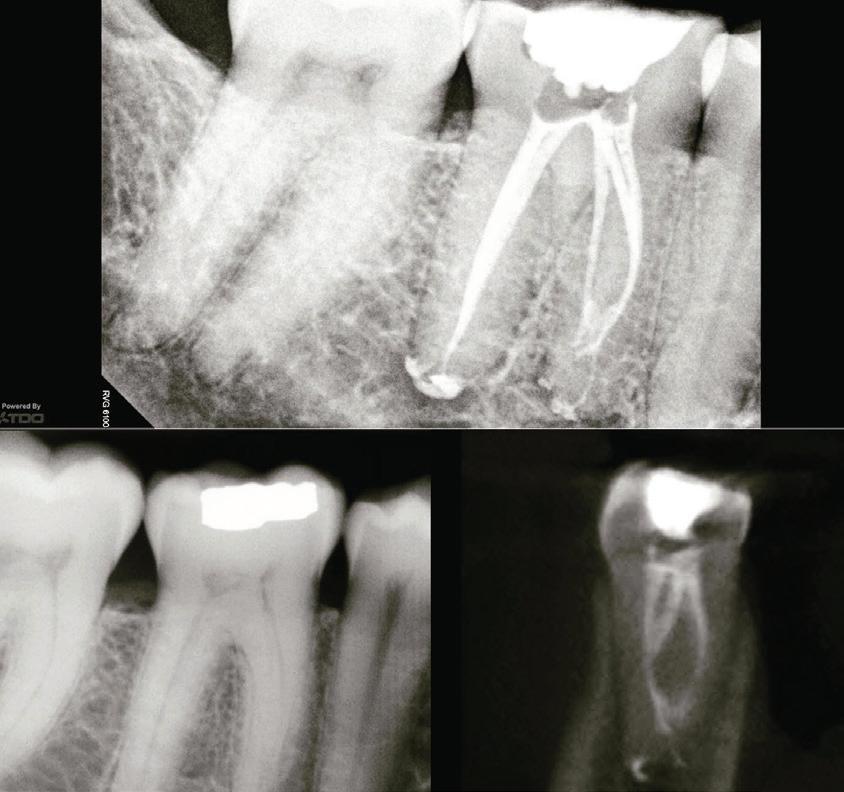

A smooth, well-informed referral will give the patient a better treatment experience when being referred by a general dentist or dental specialist to an endodontist. As with anything medical, the more information an endodontist has, the better the diagnosis and treatment. When some patients hear the word root canal, they shut down and become unreliable information sources. In my experience, many patients do not even know what an endo-

dontist is. The dentist must help this transition by introducing the patient to an informative referral. The endodontist must see the problem and the result desired. I think there are three parts to referring the patient.

First, what is happening or has happened to initiate the referral? Second, prepare the patient for a visit. Third, what will the patient do to restore the tooth when the endodontic care has been completed? Whenever possible, the referring dentist should have a diagnosis and recommended treatment plan for the teeth to get root canal therapy. This can be simple and obvious or a guessing game for everyone when (for example) the patient has a hot tooth in a quadrant where three teeth just had new crowns. Even if your experience with the patient was a short emergency exam, you saw the patient when the symptoms were fresh. Your input is invaluable. Any referral should include the teeth in question, a brief history (this may include past restorations), planned restorations and other specialist care (such as periodontal therapy, orthodontics, etc.). The dental team should list all prescriptions given to the patient before the patient leaves the office.

Once you have the diagnosis and pain history, prepare the patient for the endodontic visit. The dental team should be able to tell the patient what an endodontist is. This portion of the communication with the patient may require the referring dentist or team to have some knowledge of the way the endodontic office serves the patient and the procedural aids the endodontic office has (such as tests to provide accurate diagnosis) to achieve the best treatment results as well as the capability of offering anxiety management.

The referrer should let the patient know that the endodontist will confirm the diagnosis, which may/will require a few screening x-rays and possibly a CBCT to identify pathology and the position of the roots and root canal spaces. Once the diagnosis has been made, the endodontist should give the patient a diagnosis, prognosis, further treatment needed to protect and seal the access and restore the tooth in function and any other viable alternatives to save the tooth. If the patient is anxious, they should be encouraged to have a consultation appointment to be given sedative and treatment options or to ease their fears. Thus informed, the patient will have the opportunity to decide if root canal therapy is or is not for them. The patient should be knowledgeable (and hopefully comfortable) about how to best save their teeth.